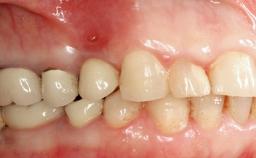

Oral implants are highly successful and offer long-term benefits, especially in the rehabilitation of edentulous patients or patients with oral defects following ablative tumor surgery (Albrektsson and coworkers 1986), and also after radiation therapy (Schiegnitz and coworkers 2014). With the number of implants placed globally going into the millions, implant dentists have observed some rare adverse events. Although carcinogenesis around implants is an exceedingly rare phenomenon, we recently reported about 15 patients treated for carcinomas adjacent to implants at our clinical department over a period of fifteen years (Moergel and coworkers 2014). The following case represents a patient of this cohort; it discusses possible risk factors and makes suggestions for a recall schedule. A 70-year-old woman was referred to our outpatient department for evaluation of a rapidly growing macroscopic alteration of the mucosa in the left mandible.

| Prosthesis Type | FDP |